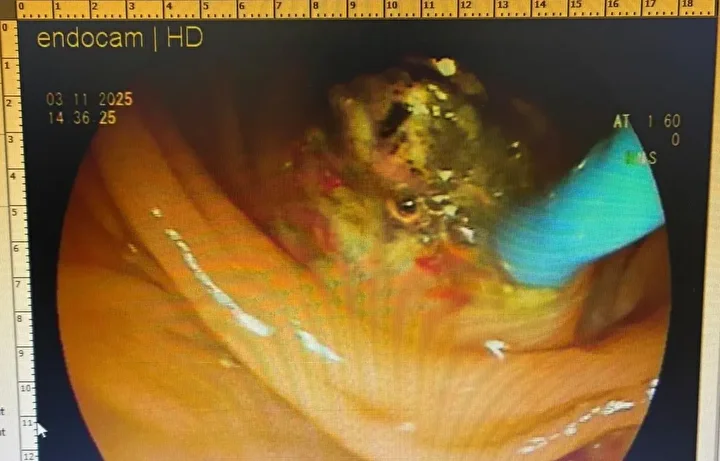

Meslek hayatında ilk kez böyle bir durum ile karşılaştığını belirten Gastroenteroloji Uzmanı Dr. Ahmet Akbay, "Hastamız karın ağrısı şikayetiyle hastanemize başvurdu. Çekmiş olduğumuz MR’da karın iç organlarının tam tersi yerleşmiş olduğunu gördük. Bu duruma ‘situs inversus totalis’ denilmektedir. Sağda olması gereken karaciğer ve safra kesesi sol tarafa ve solda olması gereken kalp ise sağ tarafa yerleşmişti. Bu hastamızda safra kanalında taş olup akut pankreatitleri geçirmekteydi. Hastamızın safra kanalındaki taşlarını ileri endoskopik yöntem olan RCP işlemiyle başarılı bir şekilde yaptık" dedi.

Tıp literatüründe çok fazla gözükmeyen bir olayla karşılaştıklarını belirten Akbay, "Bu durum dünyada ve Türkiye’de çok nadir görülen bir durumdur. Hem organların ters tarafta olması aynı zamanda safra kanalında taş ve pankreatitleri geçirmesi çok nadir görülen bir durumdur. Dolayısıyla ileri endoskopik yöntem olan RCP işlemi içinde hastanın tam ters pozisyonda, odanın dizaynını ona göre ayarladık, işlem oldukça zor olmasına rağmen başarılı bir şekilde işlemimizi yaptık, hastamız sağlığına kavuştu" şeklinde konuştu.